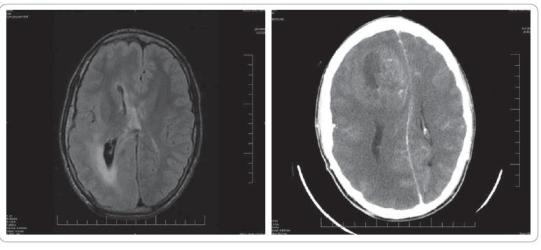

Muž, 18 let, s těžkou mentální retardací byl od novorozeneckého věku sledován pro farmakorezistentní epilepsii při pravostranné hemimegaencefalii (obr. 1). Vzhledem k multifokalitě záchvatů a nemožnosti resekce byla indikována vagová stimulace. MRI před implantací nevyslovilo podezření na nádor. Po 6 letech se u nemocného objevily kruté bolesti hlavy se zvracením. CT (MRI pro stav nemocného a vagový stimulátor kontraindikováno) prokázalo rozsáhlou expanzi frontálně vpravo, s přetlakem, smíšených denzit s kalcifikacemi a postkontrastním sycením (obr. 2). Nemocnému byla provedena subtotální resekce léze s ponecháním porce pod centrální krajinou a v hlubokých strukturách. Histologicky byl prokázán GBM. Pooperační radioterapie (bez chemoterapie) vedla k výrazné regresi rezidua tumoru. V současnosti je nemocný stabilizovaný s frustní levostrannou hemiparézou.